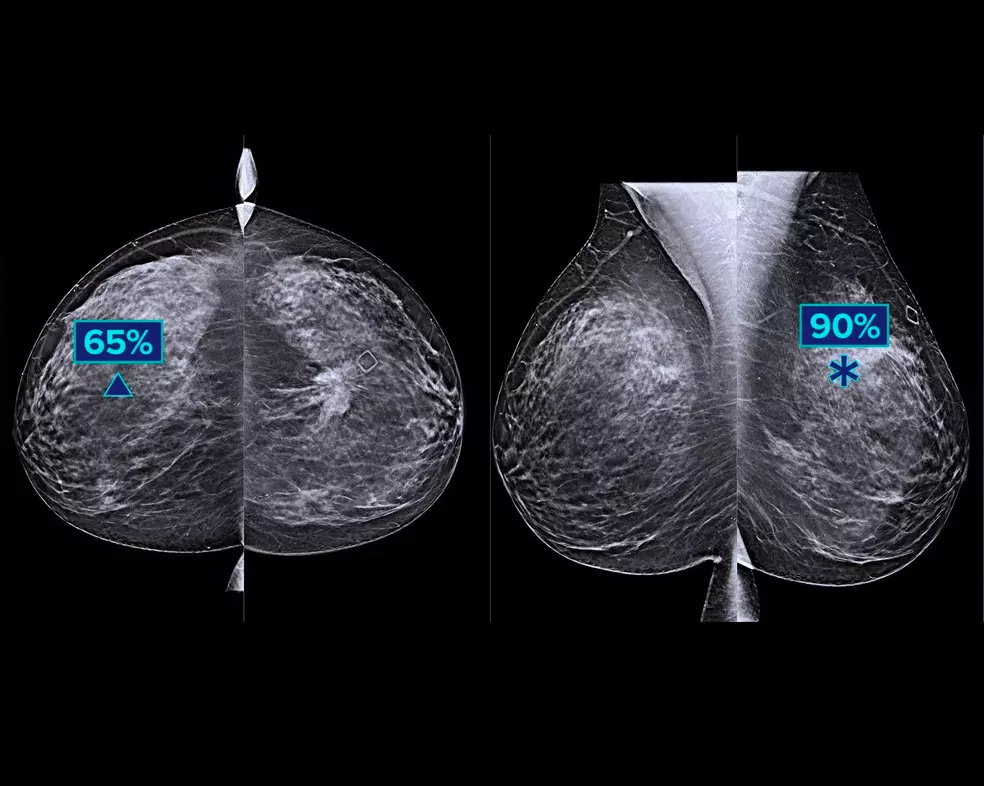

Um algoritmo de deep-learning projetado para auxiliar o desempenho de diagnóstico dos radiologistas e para detetar o cancro da mama1-3 a partir das imagens de tomossíntese obtidas com os sistemas de mamografia Dimensions® da Hologic. O algoritmo localiza lesões suscetíveis de representar cancro da mama, pesquisando em cada corte do conjunto de imagens de tomossíntese. As áreas suspeitas são destacadas para permitir uma leitura simultânea na estação de trabalho do radiologista e auxiliar na interpretação.

Estudos demonstram uma melhoria de +9% na sensibilidade observada do leitor para casos de cancro.1,2 Funciona com base em imagens de tomossíntese padrão e de alta resolução; sobreposição em imagens 3DQuorum™ SmartSlices e imagens 2D sintetizadas.

O algoritmo procura os 3 principais grupos de lesões suspeitas: calcificações; massas, densidades e distorções, assim como qualquer combinação destas lesões. Os resultados podem variar em diferentes estações de trabalho de leitura.